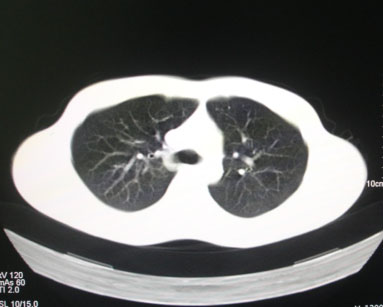

标题: CT26938:单发肺窗

病人17岁。咳嗽伴血丝痰2年?外院x片示左上肺椭圆形影,疑胸腺瘤

左肺尖见占位,建议上传纵隔窗及向上扫描。

左上纵隔占位性病变?